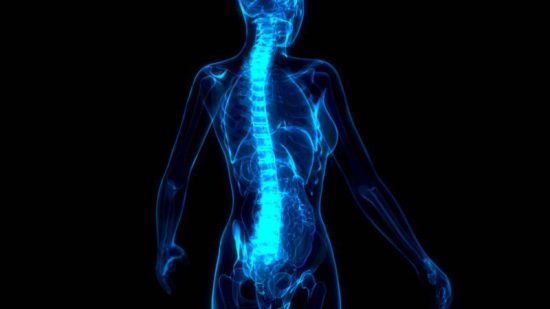

La artrosis afecta de forma frecuente a la columna vertebral, haciendo que las crisis de lumbago, lumbalgia y dolor en cervicales aumente de forma exponencial a partir de los 40 años. Si la artrosis es avanzada, no hay que esperar a que desaparezca, pero sí encontrar un remedio para que el dolor no sea un limitante para el día a día.

Con este objetivo se desarrolló la rizólisis por radiofrecuencia, un procedimiento percutáneo que actúa selectivamente sobre la zona dolorosa, de forma parecida a cuando un dentista elimina el dolor de una muela. Consiste en eliminar temporalmente las ramas de los nervios sensitivos con el envío de energía térmica por una sonda de radiofrecuencia, a través de una aguja guiada por rayos X.

Al ser un procedimiento mínimamente invasivo, la rizólisis supone un método seguro de disminuir considerablemente el dolor lumbar, cervical y dorsal. Para realizar este tratamiento se utiliza anestesia local, y quizás algo de sedación, no siendo necesario ningún tipo de cirugía ni ingreso. El procedimiento demora 15-30 minutos y tiene una duración media de 12 meses.